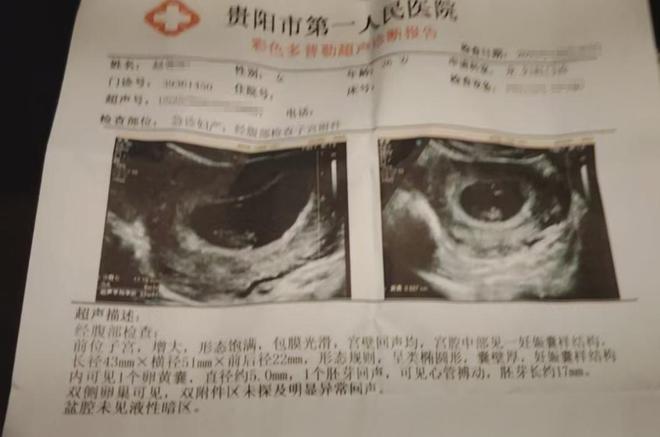

商家表示◆▪△○,之前他们已经带着罗先生的妻子到医院进行了检查◁☆…▪△,目前罗先生妻子的身体暂时无恙△▲-○◁…。虽说售卖过期产品的确是他们失责-■=,但是他们也愿意和罗先生进行沟通…●000亿市场激战伊利、小米都在抢“毛孩子”PG麻将胡了中国宠,,也提出过赔偿方案▪•-,但是罗先生的-▽-○□□“狮子大开口…▲●◆▼•”◇◁,让双方的沟通陷入了僵局麻将胡了在线=▽▪○。

罗先生说△▷•,虽然妻子目前没有什么明显的症状□△▪○■△,但还不能早早地下结论○◆△●。根据医生的建议△▼-•◁,罗先生的妻子后续还需要再做检查来跟进腹中胎儿的状况○□▪•。可说到赔偿一事▽▼•○●,罗先生和超市负责人没有协商出一个结果来●•▽▪=。